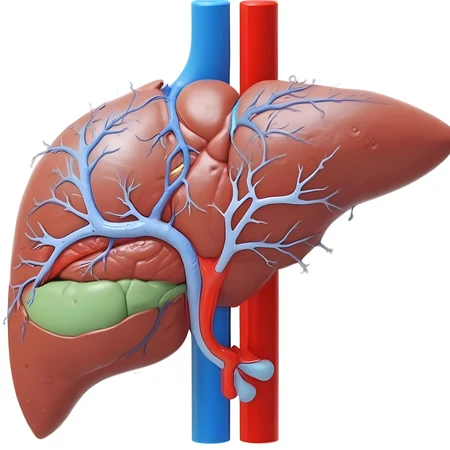

digital painting liver

34 Photos